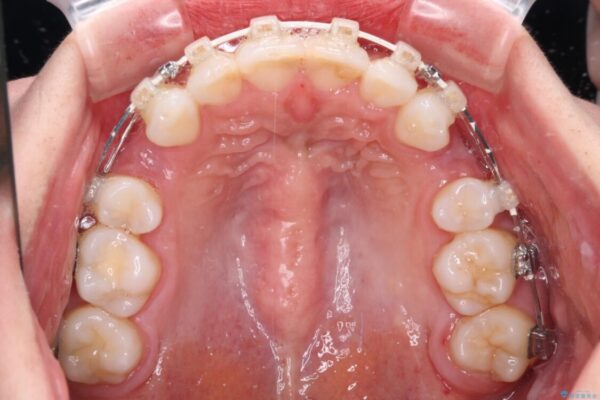

治療後について

奥歯の咬み合わせ改善には1年ほどの期間と処置中の噛みにくさを強いることとなりましたが、抜歯後はスムーズに治療を完了させることができました。

歯ぎしりの際に奥歯が干渉していた咬み合わせも理想的な状態に改善できました。

治療後

• 【モニター】出っ歯と咬み合わせを改善 ワイヤー装置の抜歯矯正 治療後画像